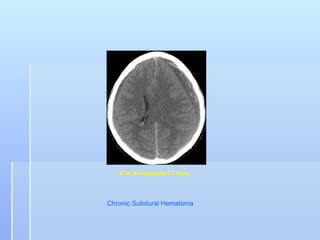

8.3a. Non-contrast CT Brain

Chronic Subdural Hematoma

8.3a. Non-contrast CTBrain Chronic Subdural Hematoma